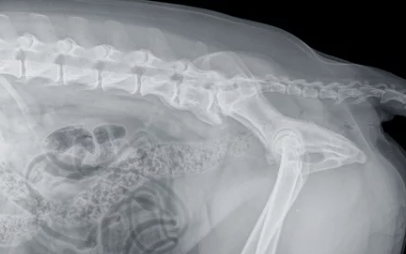

✔ 정기적으로 신경 반응 검사 및 엑스레이 검사 받기

✔ 수술 전 MRI 검사가 필수이며, 비용이 별도로 발생함